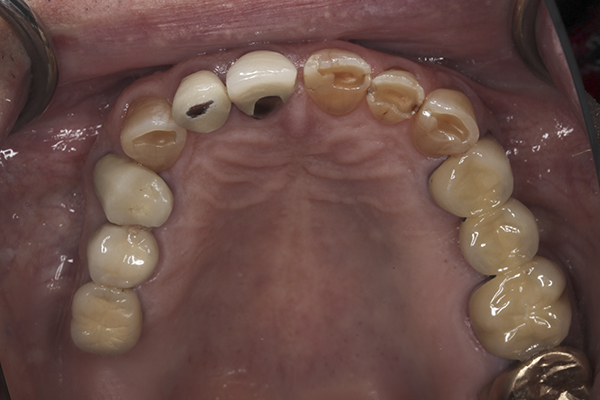

(15.) Preoperative maxillary, occlusal view.

Figure 15

(41.) Postoperative maxillary occlusal view. Note the composite tops on teeth Nos. 12 through 14.

Figure 41